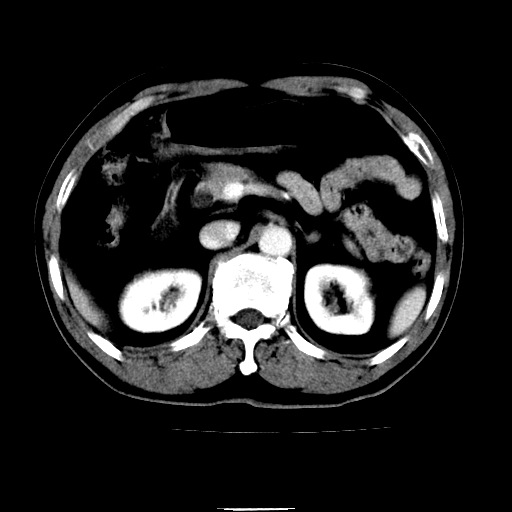

以下是引用chenqiong在2010-3-25 20:56:00的发言:[br]1、胆囊炎,胆囊息肉[br]2、肝内胆管及胆总管扩张,胆总管下端结石[br]3、十二指肠乳头旁憩室

以下是引用zxl51642在2010-3-26 10:47:00的发言:[br]胆囊炎,胆囊息肉,胆总管扩张,但未看到明显肿块,肝内胆管扩张不像恶性,炎性狭窄或阴性结石可能吧,建议mrcp,右肾小囊肿